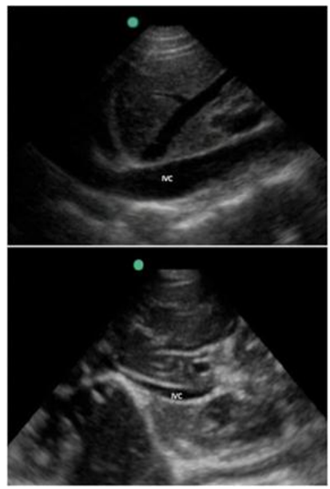

prolongado. Foi realizado ultrassom dirigido (POCUS) de leito

apresentado na imagem a seguir, demonstrando a veia cava

inferior na expiração e na inspiração, além do ventrículo

esquerdo hiperdinâmico com cavidades pequenas e ausência

de derrame pericárdico ou outras anormalidades estruturais

significativas.

Com base nos achados do ultrassom e na avaliação clínica, qual é a interpretação fisiopatológica mais provável e qual conduta deve ser realizada inicialmente?